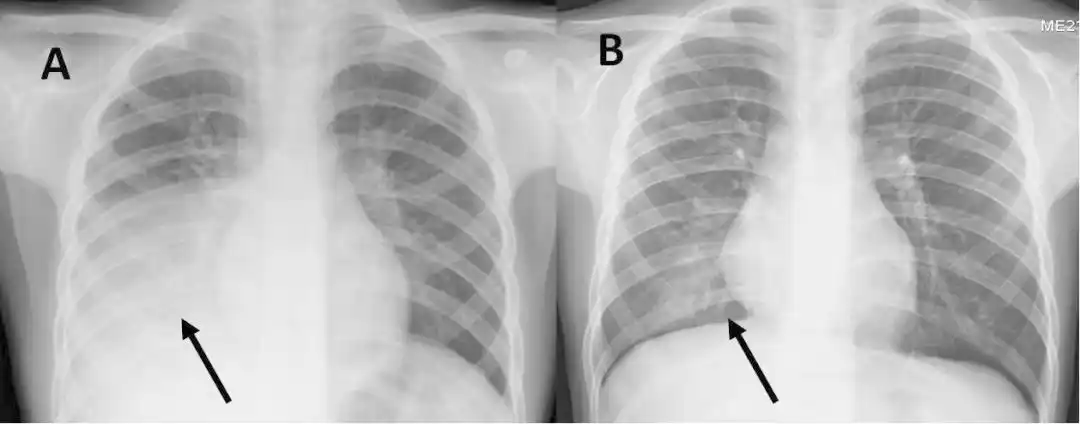

这几组患儿胸片是肺炎还是正常影像规培医师懵了

柳河县医院儿科近两年诊治125例大叶性肺炎总结